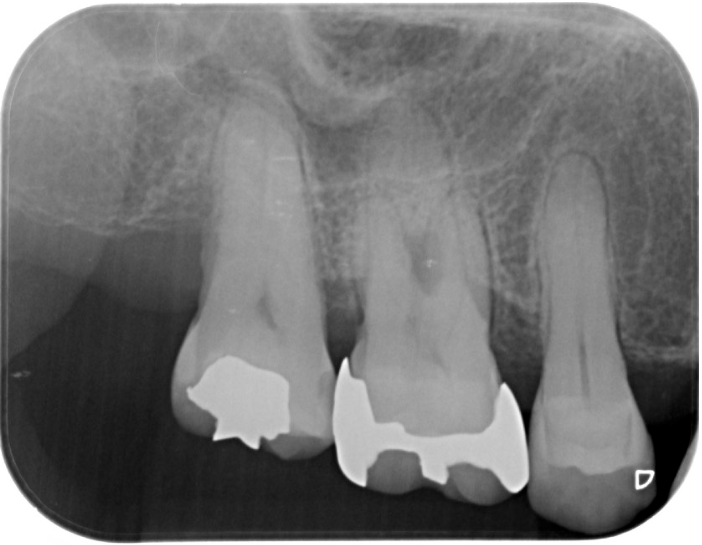

症例2

| 項目 | 詳細 |

|---|---|

| 患者様データ | 67歳 女性 |

| 来院時の主訴 | 「歯周病を治して一生自分の歯で食事を摂りたい。」 |

| 医院の診断 | 重度歯周病とう蝕 |

| 通院期間 |

1年6ヶ月 |

| 来院回数 | 10回 |

| 治療費 | 総額:480,000円(税抜) 歯周基本治療は保険適用診療 【内訳】 《保険適用診療》 歯周病検査・歯磨きや生活習慣指導・歯石取りクリーニング 《自費診療》 歯周組織再生療法240,000円(費用は範囲によって異なります。)、セラミック治療120,000円×2 |

| リスクと副作用 | メインテナンスが必要、正しい歯磨き習慣が必要不可欠 |

| ここがこだわりのポイント!☝ | 重度の歯周病の治療には長い治療期間がかかります。重症になるまでに時間がかかっている分、治るのにも時間がかかるからです。この症例の場合、患者様に頑張っていただいた結果、歯周ポケットが8mm→2mmに改善し、健康な歯周組織(骨・歯肉)を獲得することができました。 一生涯自分の歯で食事ができるよう、引き続きサポートを続けさせて頂きます!本当によく頑張って下さいました。お疲れ様でした! |